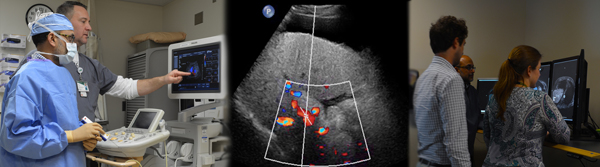

Ultrasound

Approximately 140 – 150 ultrasounds are performed per day across all our facilities. Sonographer Radiologist Assistants assist with the section workflow.

A wide variety of sonograms are performed, including:

- US contrast agent evaluation, primarily of renal and hepatic lesions

- Liver elastography

- General abdominal (hepatobiliary and renal)

- Pelvis - female

- Small parts (thyroid, testis)

- Obstetric (1st trimester)

- Lower and upper extremity arterial and venous, carotids

- Preoperative mapping prior to hemodialysis access and postoperative hemodialysis AVF and graft evaluation

- Transplant - liver, renal, and pancreas ultrasound

- About 60-70% of the examinations are vascular

Magnetic Resonance Imaging

We perform approximately 30-50 MRI scans of the abdomen and pelvis across our facilities daily. UAB is one of the largest transplant and prostate cancer centers in the southeast.